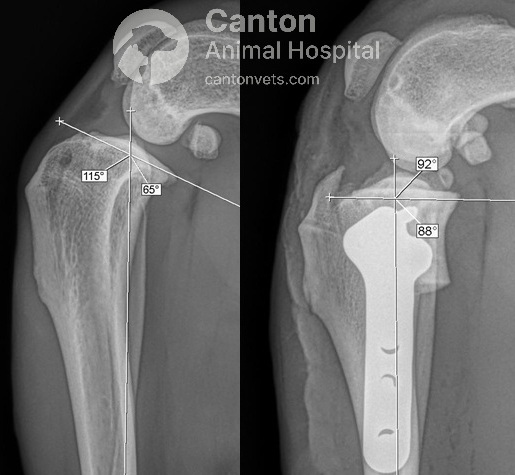

Tibial Plateau Leveling Osteotomy (TPLO) is a precise orthopedic procedure that requires detailed preoperative planning to achieve the best results. Before surgery, radiographs (X-rays) are taken to measure the dog's tibial plateau angle (TPA) and calculate the necessary rotation to achieve an optimal final angle of 5 to 6.5 degrees.

The proximal tibia (top of the shinbone) is carefully cut and rotated to change the slope of the tibial plateau.

A specialized bone plate is used to stabilize the osteotomy, ensuring proper healing.

By reducing the tibial plateau angle, the cranial tibial thrust is neutralized, allowing the dog to bear weight without abnormal joint movement.